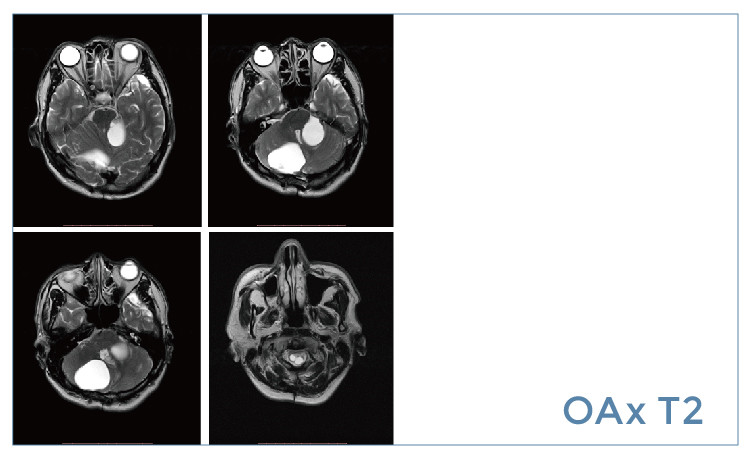

【朗润影像档案】20190614磁共振影像病例结果讨论